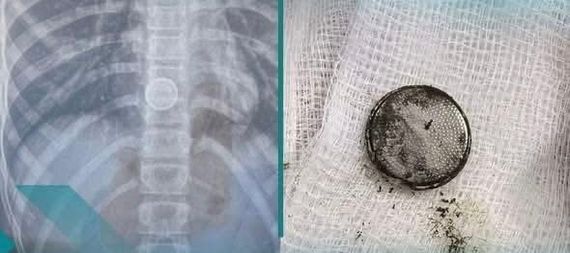

انقذ فريق طبي متخصص في مستشفى الديوانية التعليمي حياة طفلة تبلغ من العمر (12) عاماً، بعد ابتلاعها جسماً غريباً (بطارية ألعاب أطفال)، .واوضحت إدارة المستشفى أن “الفحوصات الطبية أظهرت استقرار الجسم الغريب في المريء، الأمر الذي استدعى إجراء عملية عاجلة في ساعات متأخرة من الليل، جرى خلالها استخراج البطارية بنجاح.وأكدت الإدارة أن الطفلة تتمتع حالياً بصحة جيدة”